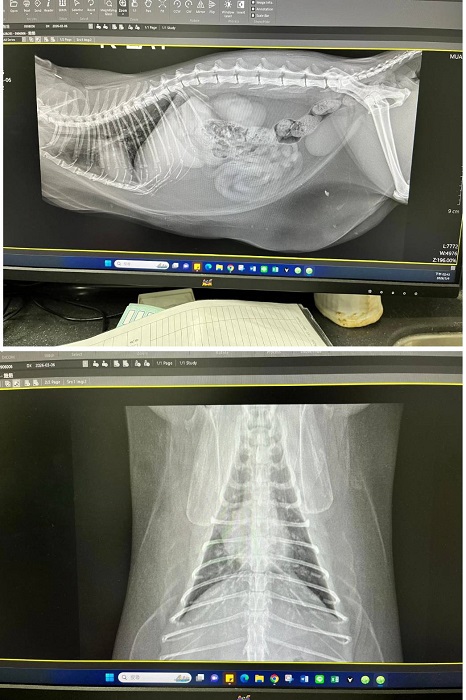

2026年3月初遷移回台北安養之家的妞妞,因照護員觀察到妞妞腹部腫大下垂,謹慎起見於是安排2026年3月6日於沐恩醫院進行看診,拍攝腹腔X光檢查,顯示胸腹部均為脂肪,屬於背部脂肪不太生成集中於腹部的體質,可不用擔心。X光看起來胰臟較大,不過質地沒有異常。同時針對胰臟較大進行超音波檢查,確認無異常。血檢也均正常。鎮靜後林院長幫妞妞修剪指甲及觸診,頭部有一側抓破皮,再請留意妞妞會不會時常抓癢。妞妞整體來說很健康,體重略重再觀察即可。本筆醫助是妞妞於2026年3月6日於沐恩醫院的醫療費用,包含看診、血檢、胸腔X光及超音波的費用。

2.拍攝腹腔X光片,顯示胸腹部均為脂肪,

屬於背部脂肪不太生成會集中於腹部的體質,可不用擔心。

X光看起來胰臟較大,不過質地沒有異常。

3.針對胰臟較大進行超音波檢查,確認無異常。